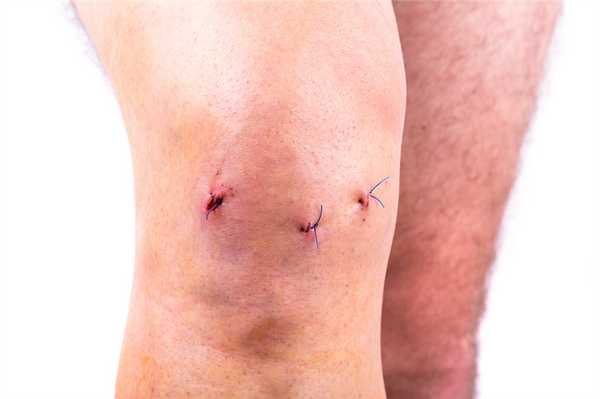

Когда еще не сняты швы.

- На асептическую обработку и перевязки пациенту нужно являться к врачу каждые два дня на протяжении 7-12 суток. Возможно, если в суставе будет выявлено скопление выпота, в момент контрольных посещений сделают его эвакуацию при помощи пункции. Швы снимаются не ранее чем по истечении недели.

Операционные раны после артроскопии коленного сустава.

Когда снимают операционные швы?

Швы на колене после операции снимают обычно на 10 сутки. За это время должно произойти окончательное сращение краев раны, зафиксированных хирургическими нитями. Если разрез незначительный и быстро зажил, вам снимут швы на 7-й день. Вообще способность к регенерации мягких тканей, которые были рассечены в момент операции, у всех людей разная. У пожилой категории пациентов или людей, страдающих диабетом, окончательное заживление может состояться только на 12-14 день.

Судя по шрамам у данного пациента не левом коленном суставе была проведена частичная замена и артроскопия. Швы выглядят хорошо.